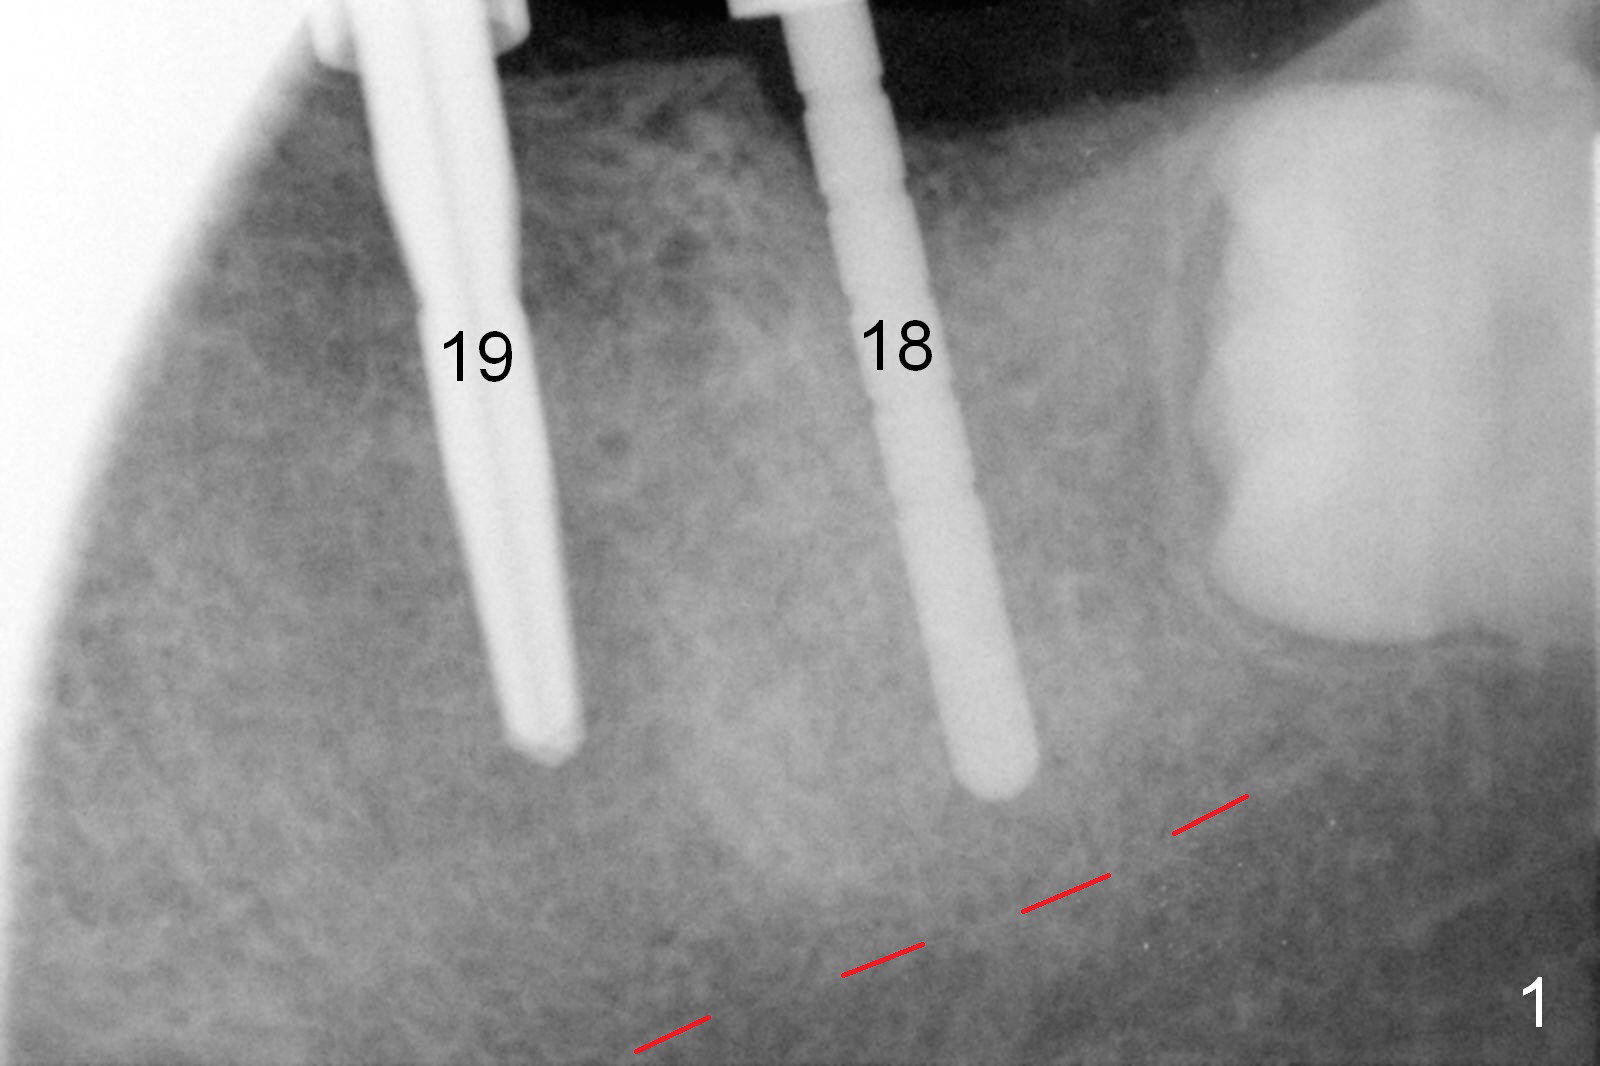

Infiltration anesthesia is enough for initial osteotomy at the site of #19 (Fig.1), but not for sectioning the tooth #18. Block anesthesia has to be administered. Fortunately it is safe to start osteotomy at #18 (~ 3 mm beyond the socket bottom, Fig.1 (red dashed line: the superior border of the Inferior Alveolar Canal (IAC))). A 4.5x14 mm implant is stable at #19, while a 5x12 mm one at #18 is not (Fig.2). Unfortunately bone graft has been placed. When the implant is removed, a 4.5x14 mm drill is used to deepen the osteotomy for 2 mm. The patient reports mild discomfort later on. Hemorrhage occurs, which is stopped when the same implant is re-placed. There is no stability. The implant is removed (Fig.3,4). More bone graft is placed, followed by collagen plug. It appears that bone graft has been pushed into the IAC (Fig.4 arrowheads). Medro dose pak is prescribed. In fact, no paresthesia is reported postop.